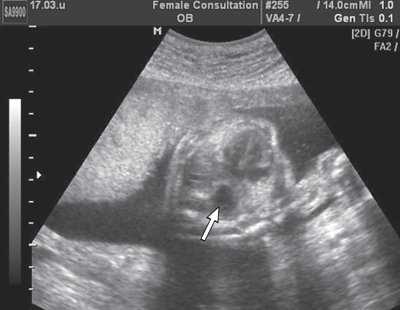

Рис. 6. Эхограмма поперечного сечения грудной клетки плода. Стрелкой указан желудок плода, расположенный в его грудной клетке.

Немаловажное значение для оценки лицевых структур плода и четкой идентификации выявленных изменений имело дополнительное использование трехмерной эхографии [3]. Специфические изменения лица плода были заметны "с первого взгляда". При анализе объемных реконструкций была четко видна гипоплазированная нижняя челюсть и близко расположенные глазные яблоки (гипотелоризм) (рис. 7, 8). Аномалий развития других органов не выявлено.